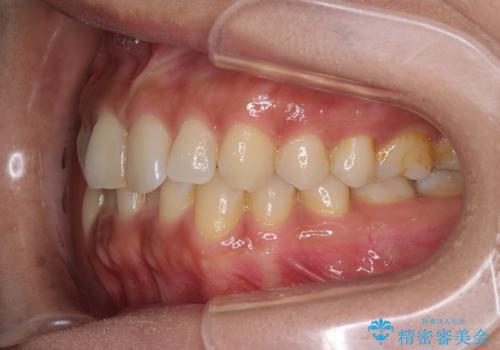

沖縄から飛行機で通院 インビザラインによる矯正治療

- 患者様

- 30代女性

- 矯正装置

- インビザライン

- 定期的に東京に来るので、沖縄から矯正治療で通院したいとのことで来院された患者様です。

歯列不正は軽度であったので、応急処置の少ないインビザラインにて矯正治療を行うこととしました。